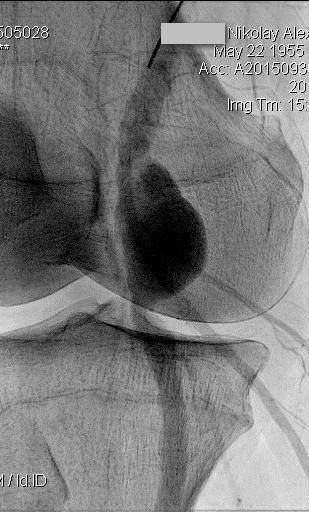

16 июня 2016 года в ЦЭЛТ, в отделении сердечно-сосудистой хирургии, состоится семинар и вебинар по самым актуальным вопросам интервенционной кардиологии и ангиологии на тему: «Современные подходы лечения пациентов со сложными поражениями артерий нижних конечностей».

В программе мероприятия: демонстрация эндоваскулярных операций в прямом эфире, лекционная часть и обсуждения докладов.